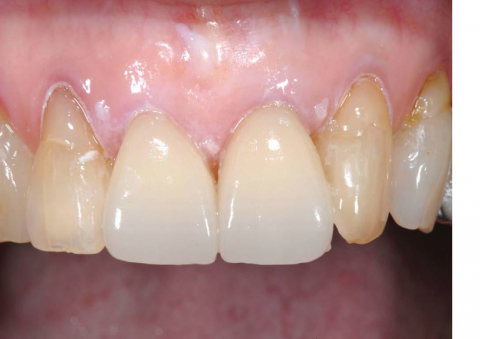

• 審美歯科

CAD / CAMシステムにより様々なマテリアルのミリング(削りだし)を正確に行うことができます。